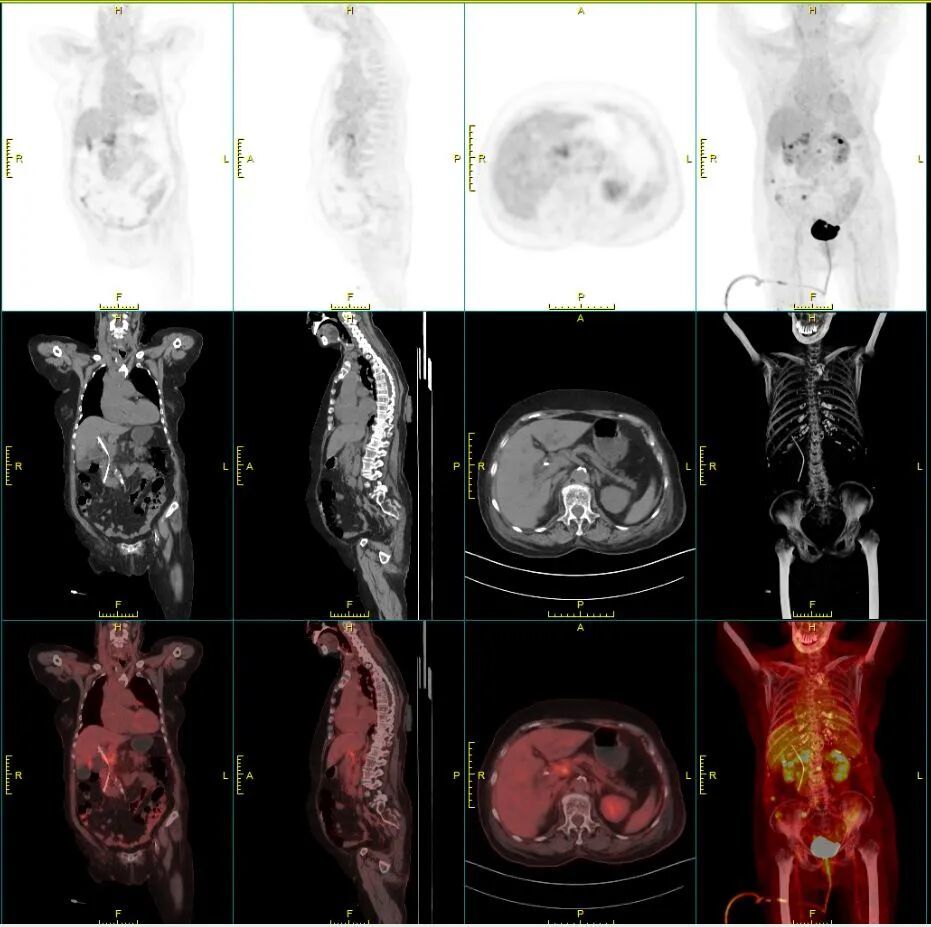

手术后第二天,胆红素就如同预计的那样出现明显下降,淀粉酶也没有明显升高。PET-CT 结果显示除了病灶、局部淋巴结和大网膜的转移外没有发现其他的远处转移灶。好消息!